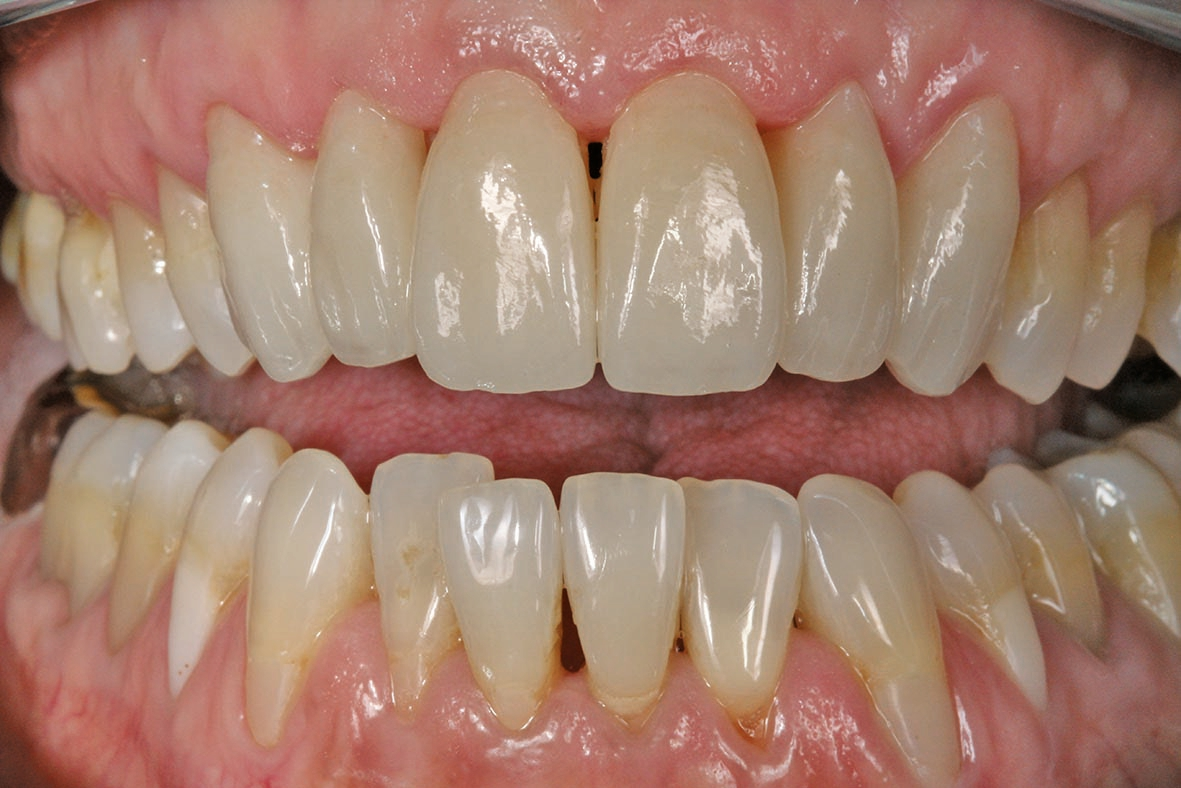

Die fertigen Veneers im Patientenmund